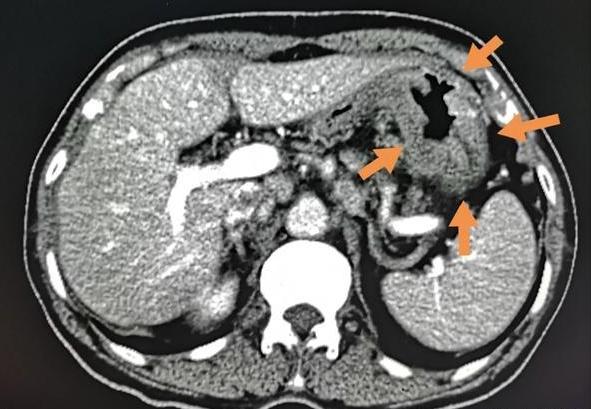

来医院全面检查后发现了右侧结肠癌:

胃镜活检为中、低分化腺癌,CT显示胃窦壁广泛增厚(箭头所示)。